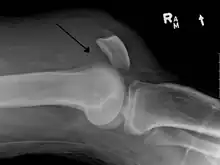

An x-ray demonstrating quadriceps tendon rupture. Note the abnormal angle of the patella and soft-tissue swelling marked by the arrow.

A quadriceps tendon rupture is a tear of the tendon that runs from the quadriceps muscle to the top of the knee cap.[1]